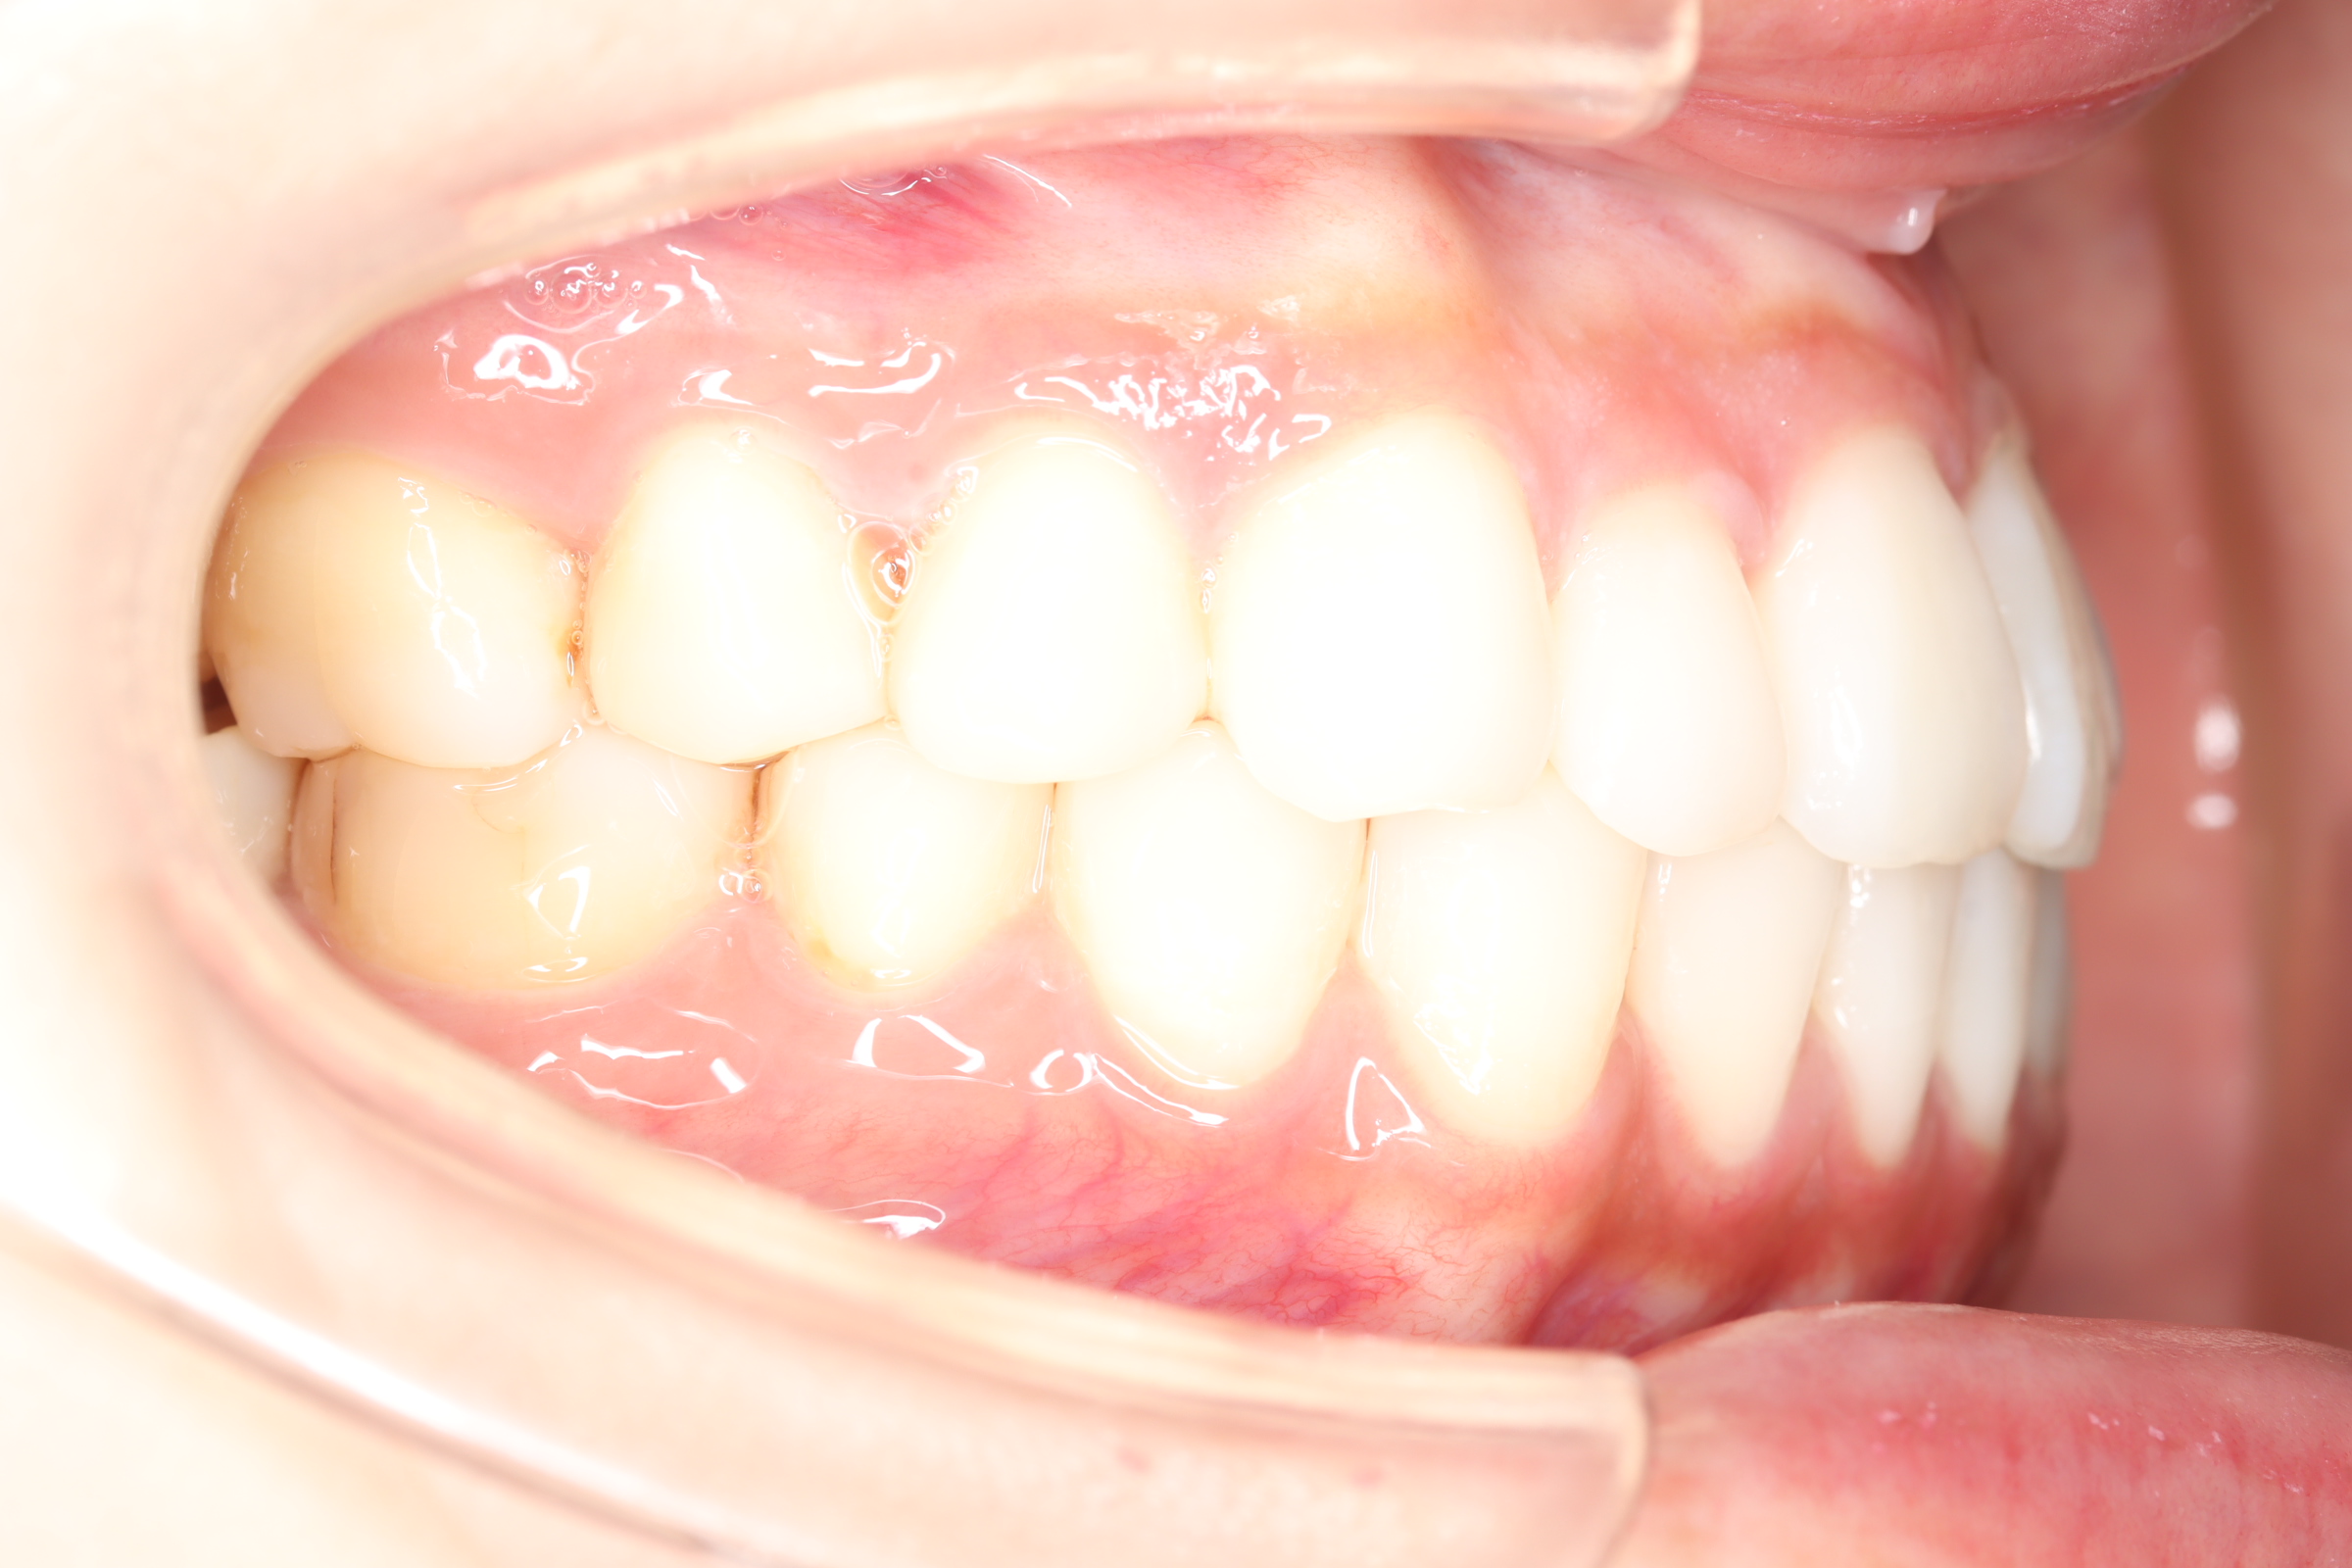

口腔内とラテラルセファログラムの変化

![]() | ![]() | ![]() |

| ↓ | ↓ | ↓ |

治療前後の解説

| 治療前 | 骨格的には受け口の患者さんですが、上顎前歯の唇側傾斜が大きく、患者さんとしては出っ歯だと思われていたパターンです。 元々口元の突出感はほとんどなかったため、歯を抜かずに上下顎ともに歯列を後方に移動させることにより主訴を改善させることとしました。 |

| 治療後 | 前歯から奥歯まで全体的に緊密な咬み合わせになっています。 治療前後のセファログラムのトレースの重ね合わせを比較すると、上下の歯列の後方移動ができ、それにより口元もよりすっきりしました。 また前歯の唇側傾斜も改善されています。 |